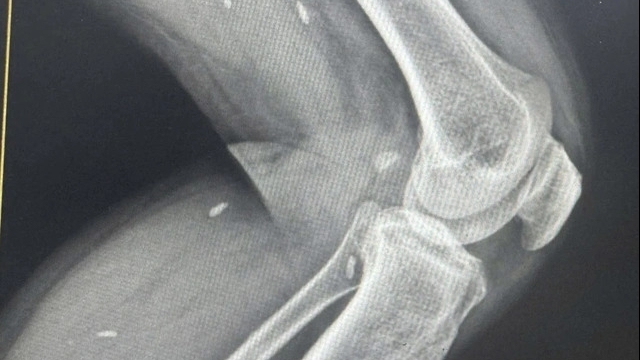

Các bác sĩ của Bệnh viện đã tích cực học tập làm chủ nhiều kỹ thuật tiên tiến có tầm cỡ quốc gia và quốc tế như: phẫu thuật và can thiệp tim mạch, phẫu thuật thần kinh, sọ não, chấn thương chỉnh hình, nội soi can thiệp tiêu hóa, phẫu thuật và điều trị sản phụ khoa…

Đặc biệt, theo GS Thành, sự phối hợp chặt chẽ giữa các chuyên khoa như Sản – Tim mạch đã cứu nhiều sản phụ mắc bệnh tim bẩm sinh sinh con thành công; hay Tim mạch – Hồi sức tích cực – Ngoại tổng hợp – Gây mê hồi sức đã cứu sống những bệnh nhân tưởng mười mươi là chết, như trường hợp bệnh nhân bị thanh thép đâm thấu tim; bệnh nhân bị dao đâm xuyên cổ…